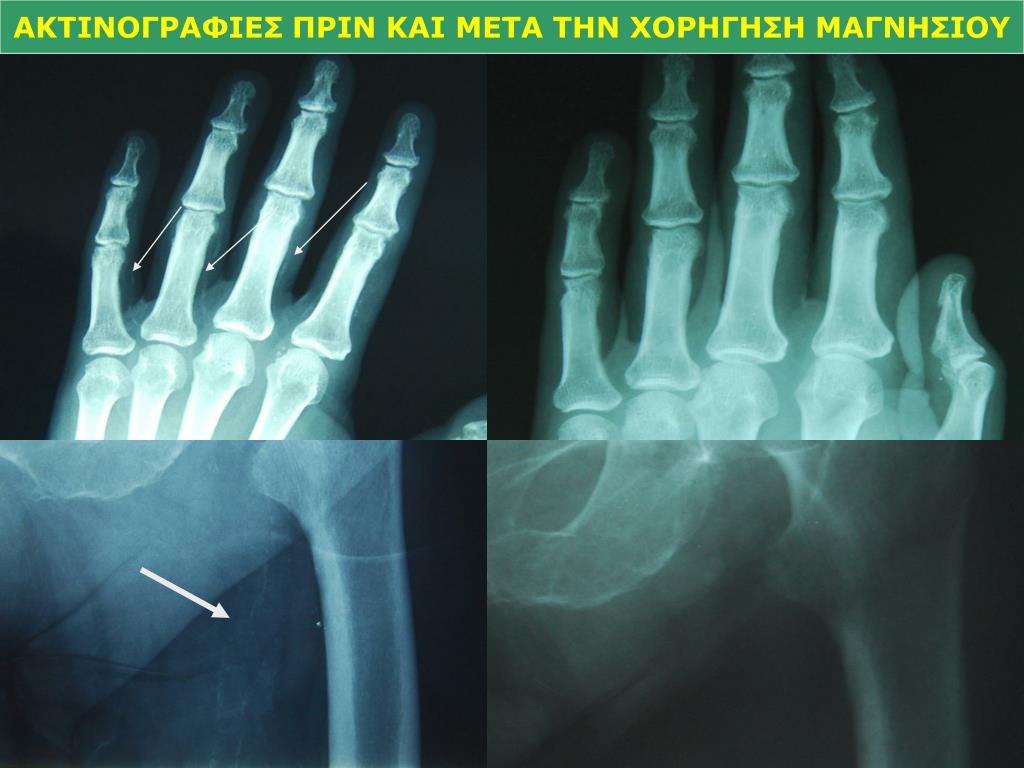

30. 32 AIK ασθενείς MgC03 + Ca acetate 27 AIK ασθενείς Ca acetate (ομάδα ελέγχου) Ακτινολογικός έλεγχος για ασβεστώσεις αγγείων Παρακολούθηση για 12 μήνες Έκβαση αρτηριακών επασβεστώσεων Μέσες τιμές 12μήνου Παράγοντες μη επιδείνωσης 170 ΠΑΝΝΕΛΗΝΙΟ ΣΥΝΕΔΡΙΟ ΝΕΦΡΟΛΟΓΙΑΣ, 2012

31. ΑΚΤΙΝΟΓΡΑΦΙΕΣ ΠΡΙΝ ΚΑΙ ΜΕΤΑ ΤΗΝ ΧΟΡΗΓΗΣΗ ΜΑΓΝΗΣΙΟΥ